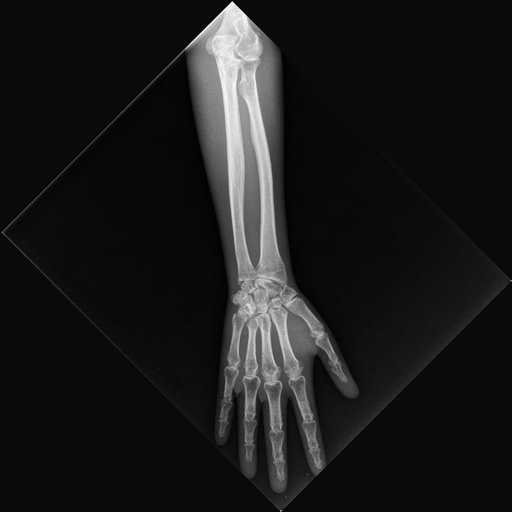

ERLERZIMMER Röntgenphantom Unterarm, opak

Röntgenphantom Unterarm, opak

Dieses Röntgen-Teilphantom bietet Ihnen die einmalige Möglichkeit, reale Röntgenaufnahmen so oft Sie wollen zu wiederholen. Das Modell enthält echte menschliche Knochen und erlaubt so, echte Aufnahmen zu machen. Das Modell eignet sich perfekt für Schulen und Ausbildungsstätten, aber natürlich auch für die Medizintechnik, da verschiedene Einstellungen mit dem gleichen Körperteil wieder und wieder ausprobiert werden kann, ohne dass eine Gefährdung des Patienten in Kauf genommen werden muss. Das Modell ist in transparentem Kunststoff fest eingebettet. Diese Ausführung ist mit einem undurchsichtigen Lack versehen, so dass die inneren Strukturen nicht zu erkennen sind. Bei diesem Modell handelt es sich um ein handgefertigtes Einzelstück, das in seiner Größe und Ausführung abweichen kann. Bedingt durch das Fertigungsverfahren können im Innern des Phantoms Verfärbungen oder Risse vorhanden sein, dies ist produktionsbedingt und stellt keinen Defekt dar. Der Verkauf dieses Modells erfolgt nur gegen Nachweis der medizinischen Verwendung.

Hand mit Unterarm und Ellenbogen. Inklusive Transportkoffer

7.516,52 € 7516.52 EUR

ERLERZIMMER Röntgenphantom Unterarm, transparent

Röntgenphantom Unterarm, transparent

Dieses Röntgen-Teilphantom bietet Ihnen die einmalige Möglichkeit, reale Röntgenaufnahmen so oft Sie wollen zu wiederholen. Das Modell enthält echte menschliche Knochen und erlaubt so, echte Aufnahmen zu machen. Das Modell eignet sich perfekt für Schulen und Ausbildungsstätten, aber natürlich auch für die Medizintechnik, da verschiedene Einstellungen mit dem gleichen Körperteil wieder und wieder ausprobiert werden kann, ohne dass eine Gefährdung des Patienten in Kauf genommen werden muss. Das Modell ist in transparentem Kunststoff fest eingebettet. Bei diesem Modell handelt es sich um ein handgefertigtes Einzelstück, das in seiner Größe und Ausführung abweichen kann. Bedingt durch das Fertigungsverfahren können im Innern des Phantoms Verfärbungen oder Risse vorhanden sein, dies ist produktionsbedingt und stellt keinen Defekt dar. Der Verkauf dieses Modells erfolgt nur gegen Nachweis der medizinischen Verwendung.

Hand mit Unterarm und Ellenbogen.

Inklusive Transportkoffer

7.720,86 € 7720.86 EUR